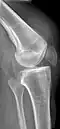

Quadriceps tendon rupture in plain X-ray -